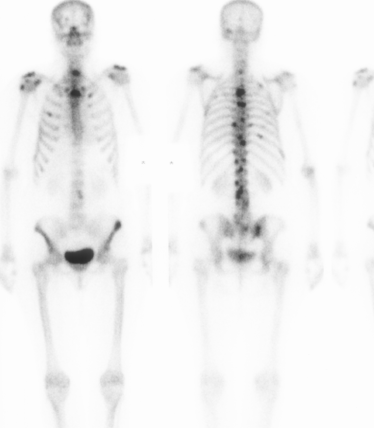

Bone Scan

Most sensitive screening tool

False negative 10% - Myeloma / Melanoma / Renal cell carcinoma